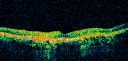

OCT SCAN: The OCT scan show retinal atrophy. Photos confirm clinical findings.